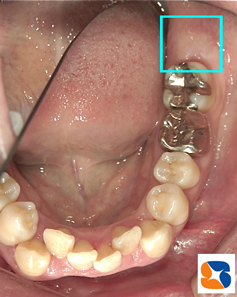

一部分すら見えない親知らずの抜歯

コラム「一部分すら見えない親知らずの抜歯」の画像